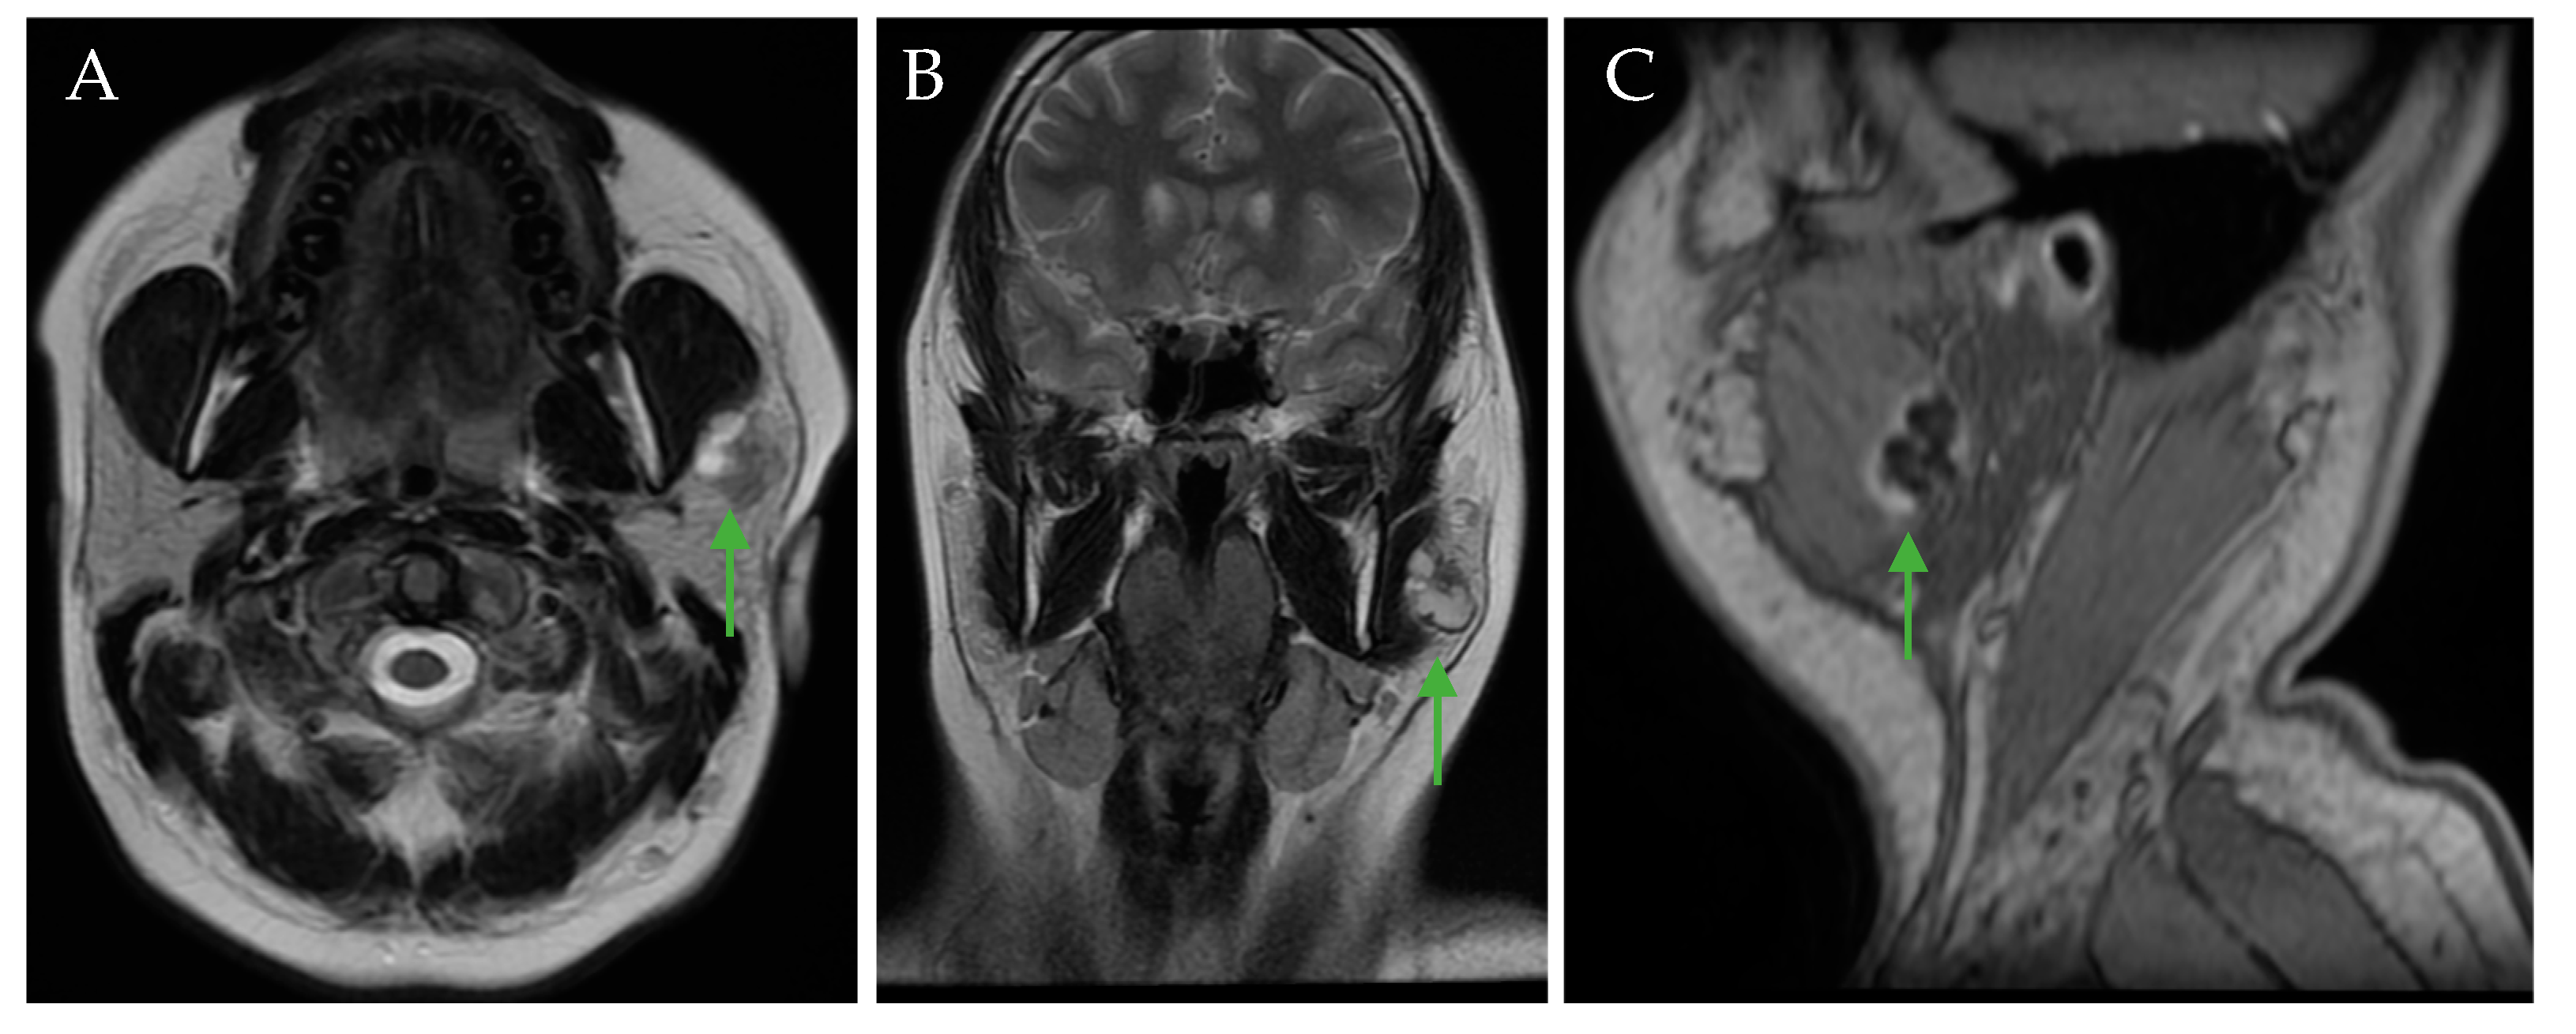

| 30 | 2024 | Current report | 23/F | Lyme disease | 2 × 1.5 cm | Left | Swelling of neck Pain | Biopsy US CT IRM | Superficial parotidectomy and selective neck dissection | Inflammatory lymph node/squamous cell carcinoma |